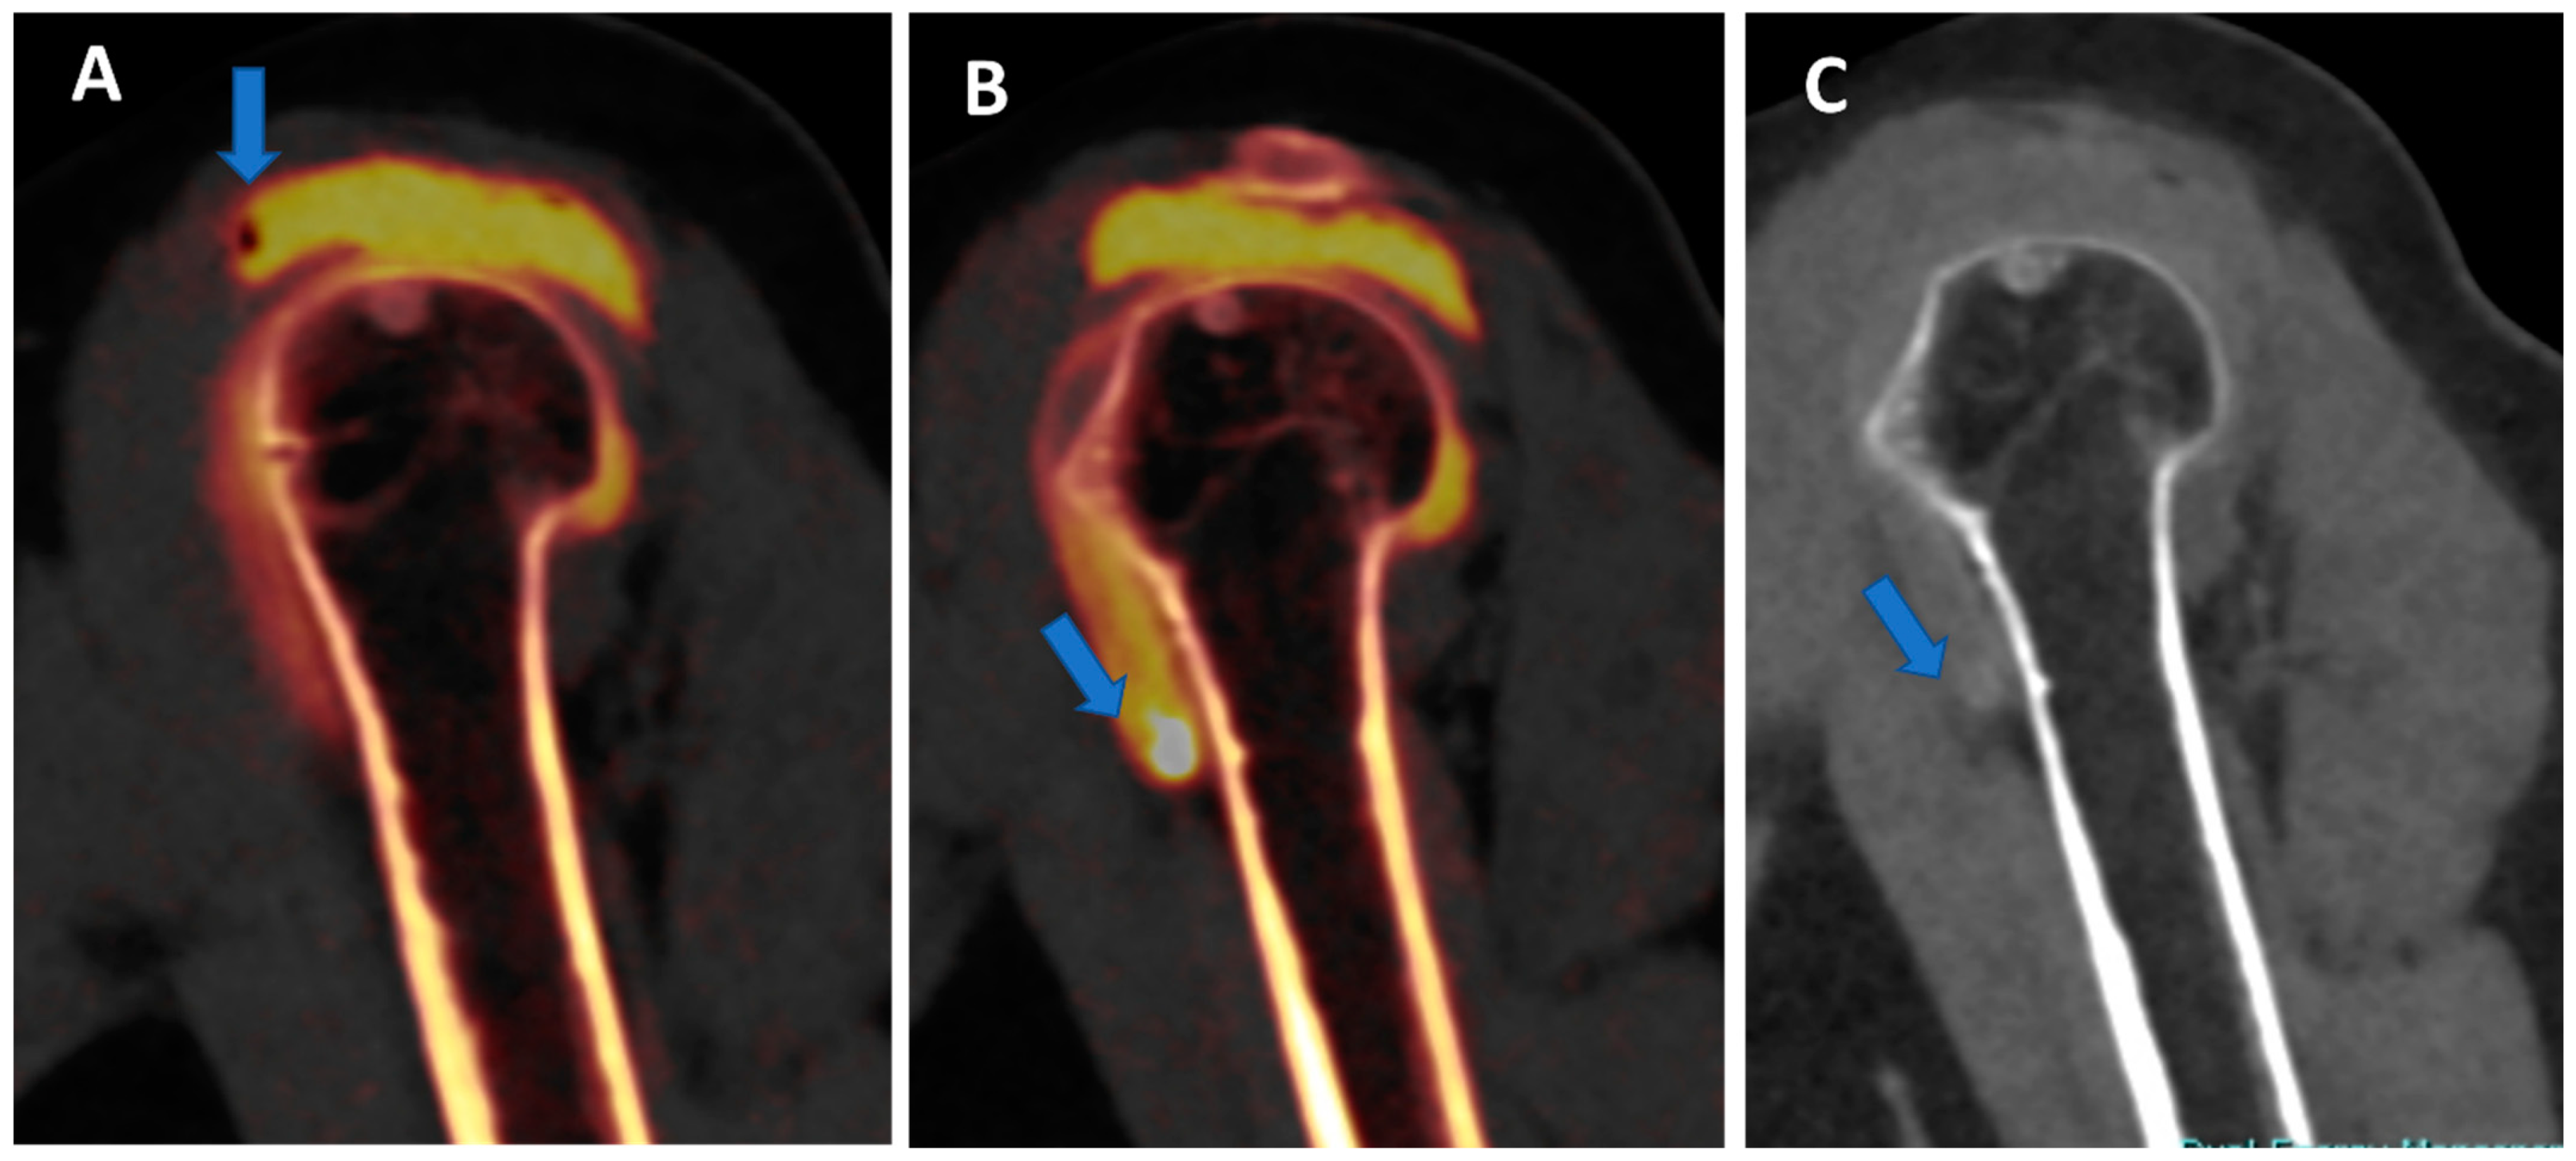

Figure 1.

Recurrent anterior shoulder dislocation in a previously operated patient. By using multiple applications, DECTA can help in the diagnosis of anterior shoulder dislocation, potentially representing a “one-stop one-shop” procedure. A blended virtual 120 kVp axial CTA image (A) shows anterior labral and glenoid rim disruption (arrow). A VNC image on the axial (B) and sagittal (E) planes helps in the evaluation of bone morphology, allowing correct glenoid surface measurement (arrow). In the axial iodine map (C), it is possible to better evaluate the morphology of the anterior labrum (arrow). In the axial BME 2D superimposed image (D), it is possible to recognize edema of the anterior glenoid rim (blue arrow) and subtle edema of the posterior aspect of the humeral head (white arrow), which is consistent with recent recurrent dislocation.

Figure 6.

Traumatic anterior shoulder dislocation with rotator cuff complete tear and Hill Sachs lesion. On the 2D 1 mm axial and coronal reconstructed VNCa images (A,B), a subtle depression of the posterior aspect of the humeral head is visible, with mild edema coded in green on the superimposed map (arrow). The 3D VNCa image (C) clearly shows the passage of contrast material in the sub-acromial space (arrow). On the coronal 1 mm reconstructed iodine map image (D), the complete rupture of the rotator cuff is beautifully confirmed (arrow). On the sagittal LNC images (E,F), it is possible to identify (arrow on (F)) and quantify (ROI on (E)) the presence of atrophy of the muscle belly.

In clinical practice, BME maps reconstructed from VNCa imaging could be employed to detect bone marrow lesions around the imaged joints. Although iodinated contrast material could generate some artifacts in the adjacent areas, the presence of BME can still be visualized. For example, in the case of shoulder trauma with doubtful dislocation, the presence of BME on the posterior aspect of the humeral head may help corroborate the diagnosis of a Hill-Sachs lesion (Figure 1 and Figure 6). In addition, BME around the joint, with or without erosions, can be found in inflammatory diseases such as septic or aseptic arthritis [31,32,33] (Figure 7).